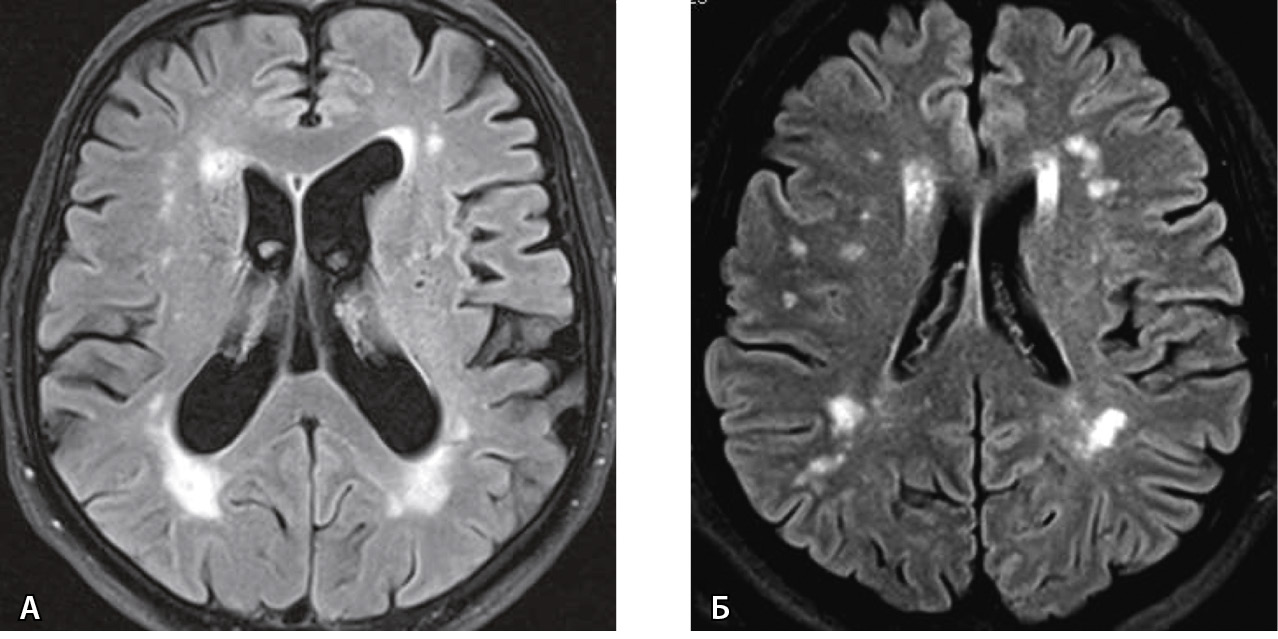

Определены предикторы для прогнозирования 2-й и более стадии перивентрикулярного и субкортикального лейкоареоза по шкале Фазекаса (рис. 1). Статистика предикторов модели отражена в табл. 3. Выявлено, что с увеличением показателя XIIа-зависимого фибринолиза вероятность 2-й и более стадии лейкоареоза возрастает, а с увеличением концентрации плазминогена – снижается. Шанс развития лейкоареоза увеличивается в 1,31 раза на каждую единицу XIIа-зависимого фибринолиза и снижается в 1,03 раза на каждую единицу плазминогена. Модель согласуется с фактическими данными (тест Хосмера – Лемешова, p = 0,638), является статистически значимой (p < 0,001) и имеет информативность Нейджелкерка R2 = 0,44.

Рис. 1. Умеренный лейкоареоз вокруг желудочков – 2-я степень по шкале Фазекаса в перивентрикулярной зоне (А) и умеренное поражение субкортикальной зоны с множественными точечными и единичными сливными очагами глиоза – 2-я степень по шкале Фазекаса в субкортикальной зоне (Б). Суммарная оценка (перивентрикулярная зона + субкортикальная зона) – 4-я степень по шкале Фазекаса